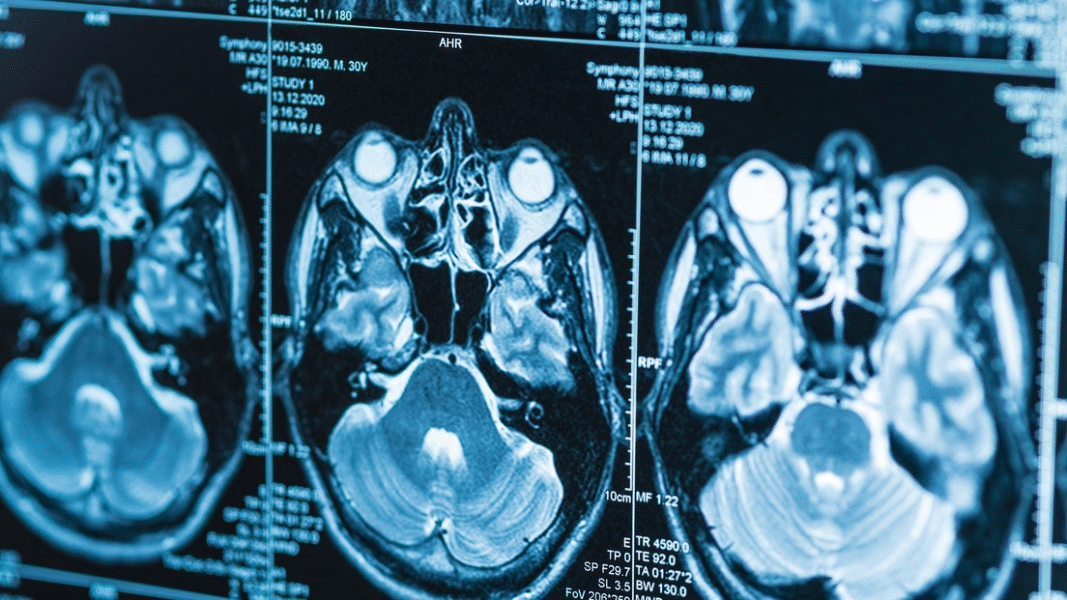

En ese sentido, la investigación, que reunió más de 12.500 escáneres cerebrales de participantes entre 17 y 95 años, buscaba precisar por qué la enfermedad de Alzheimer afecta a casi el doble de mujeres que de hombres.